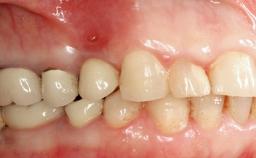

Peripheral Giant-cell Granuloma Associated with Peri-implant Tissues

Prosthesis Type FDP